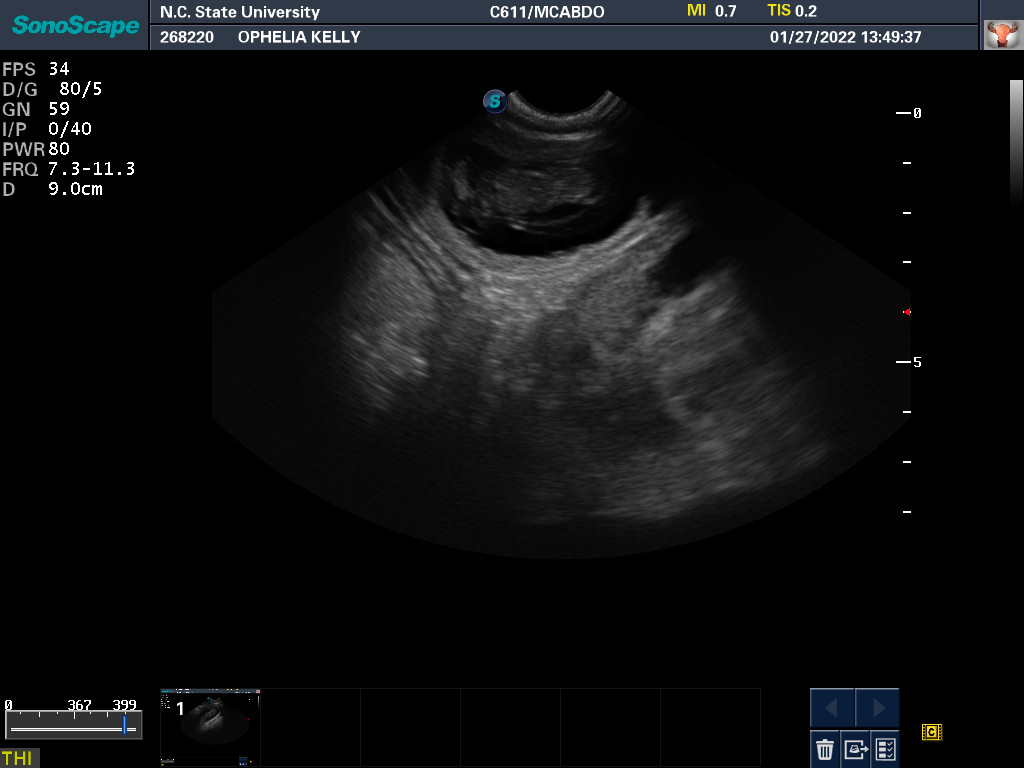

27 Jan 2022

Ultrasound today by the theriogenology (reproduction) veterinarians at NC State University showed that Ophelia is pregnant with three puppies, possibly four puppies. (It can be difficult to accurately count puppies using ultrasound.)

This morning Ophelia did not want to eat any breakfast. As I was going to Raleigh on other business, I took Ophelia to be checked out by my repro vets. After examining Ophelia, ultrasounding the puppies, and testing Ophelia's progesterone, the vet assured me that everything looked normal. When a dog has a lot of puppies, there is less room for a lot of food in the stomach. So it looks like going forward I will be feeding Ophelia lots of small meals.

The x-ray also revealed that it is unlikely that Ophelia will be able to free-whelp the puppies. The size of the skulls of the puppies is larger than Ophelia's pelvic opening. This is called fetal-pelvic misproportion (or more technically cephalopelvic disproportion), and in my opinion is the reason many Norwich have difficulty free-whelping. So we are planning on a c-section for Ophelia. From now until the c-section, every morning I will be taking Ophelia to NC State, where my repro vets will test her progesterone level and check the status of the puppies via ultrasound. When the puppies are sufficiently "cooked" (developed), they will do a c-section. Most likely this will be Thursday based upon when Ophelia ovulated.